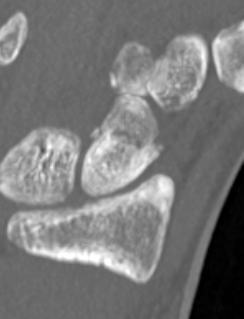

CT

Indication: any potential displacement

Position: patient prone with fully pronated hand over head

Instability

- displacement > 1mm on any film

- intra-scaphoid angle > 35o

- comminution

- proximal pole fractures

- perilunate trans-scaphoid dislocation

Scaphoid waist fracture 1 mm displaced

Scaphoid fracture with significant displacement

Scaphoid proximal pole fracture